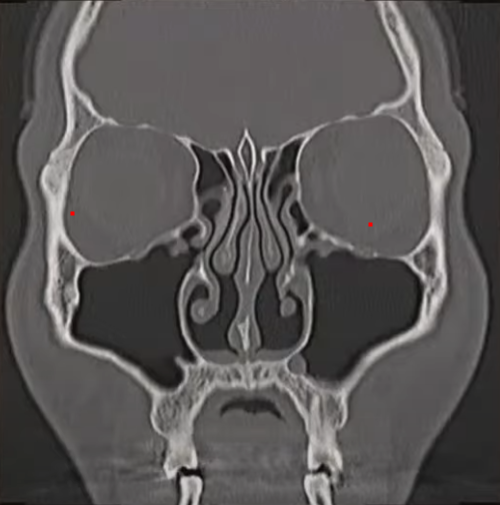

부비동은 얼굴뼈 속에 있는 공기로 채워져 있는 공간으로 부위에 따라 다음과 같이 4가지로 나누어 집니다.

부비동은 코주위의 얼굴 뼈속에 있는 빈공간을 의미하며, 이 공간들은 자연공(sinus ostia)이라는 작은 구멍을 통해 콧속과 연결되어 있고, 이 구멍을 통해 부비동 내로 공기의 환기 및 분비물의 배출이 이루어집니다.

부비동염은 주돼니 감염 위치에 따라 위에 제시된 사골동, 상악동, 전두동, 접형동 부비동염으로 분류하며, 기간에 따라 급성(4주미만), 아급성(4주~3개월), 만성(3개월이상)으로 분류하기도 합니다.